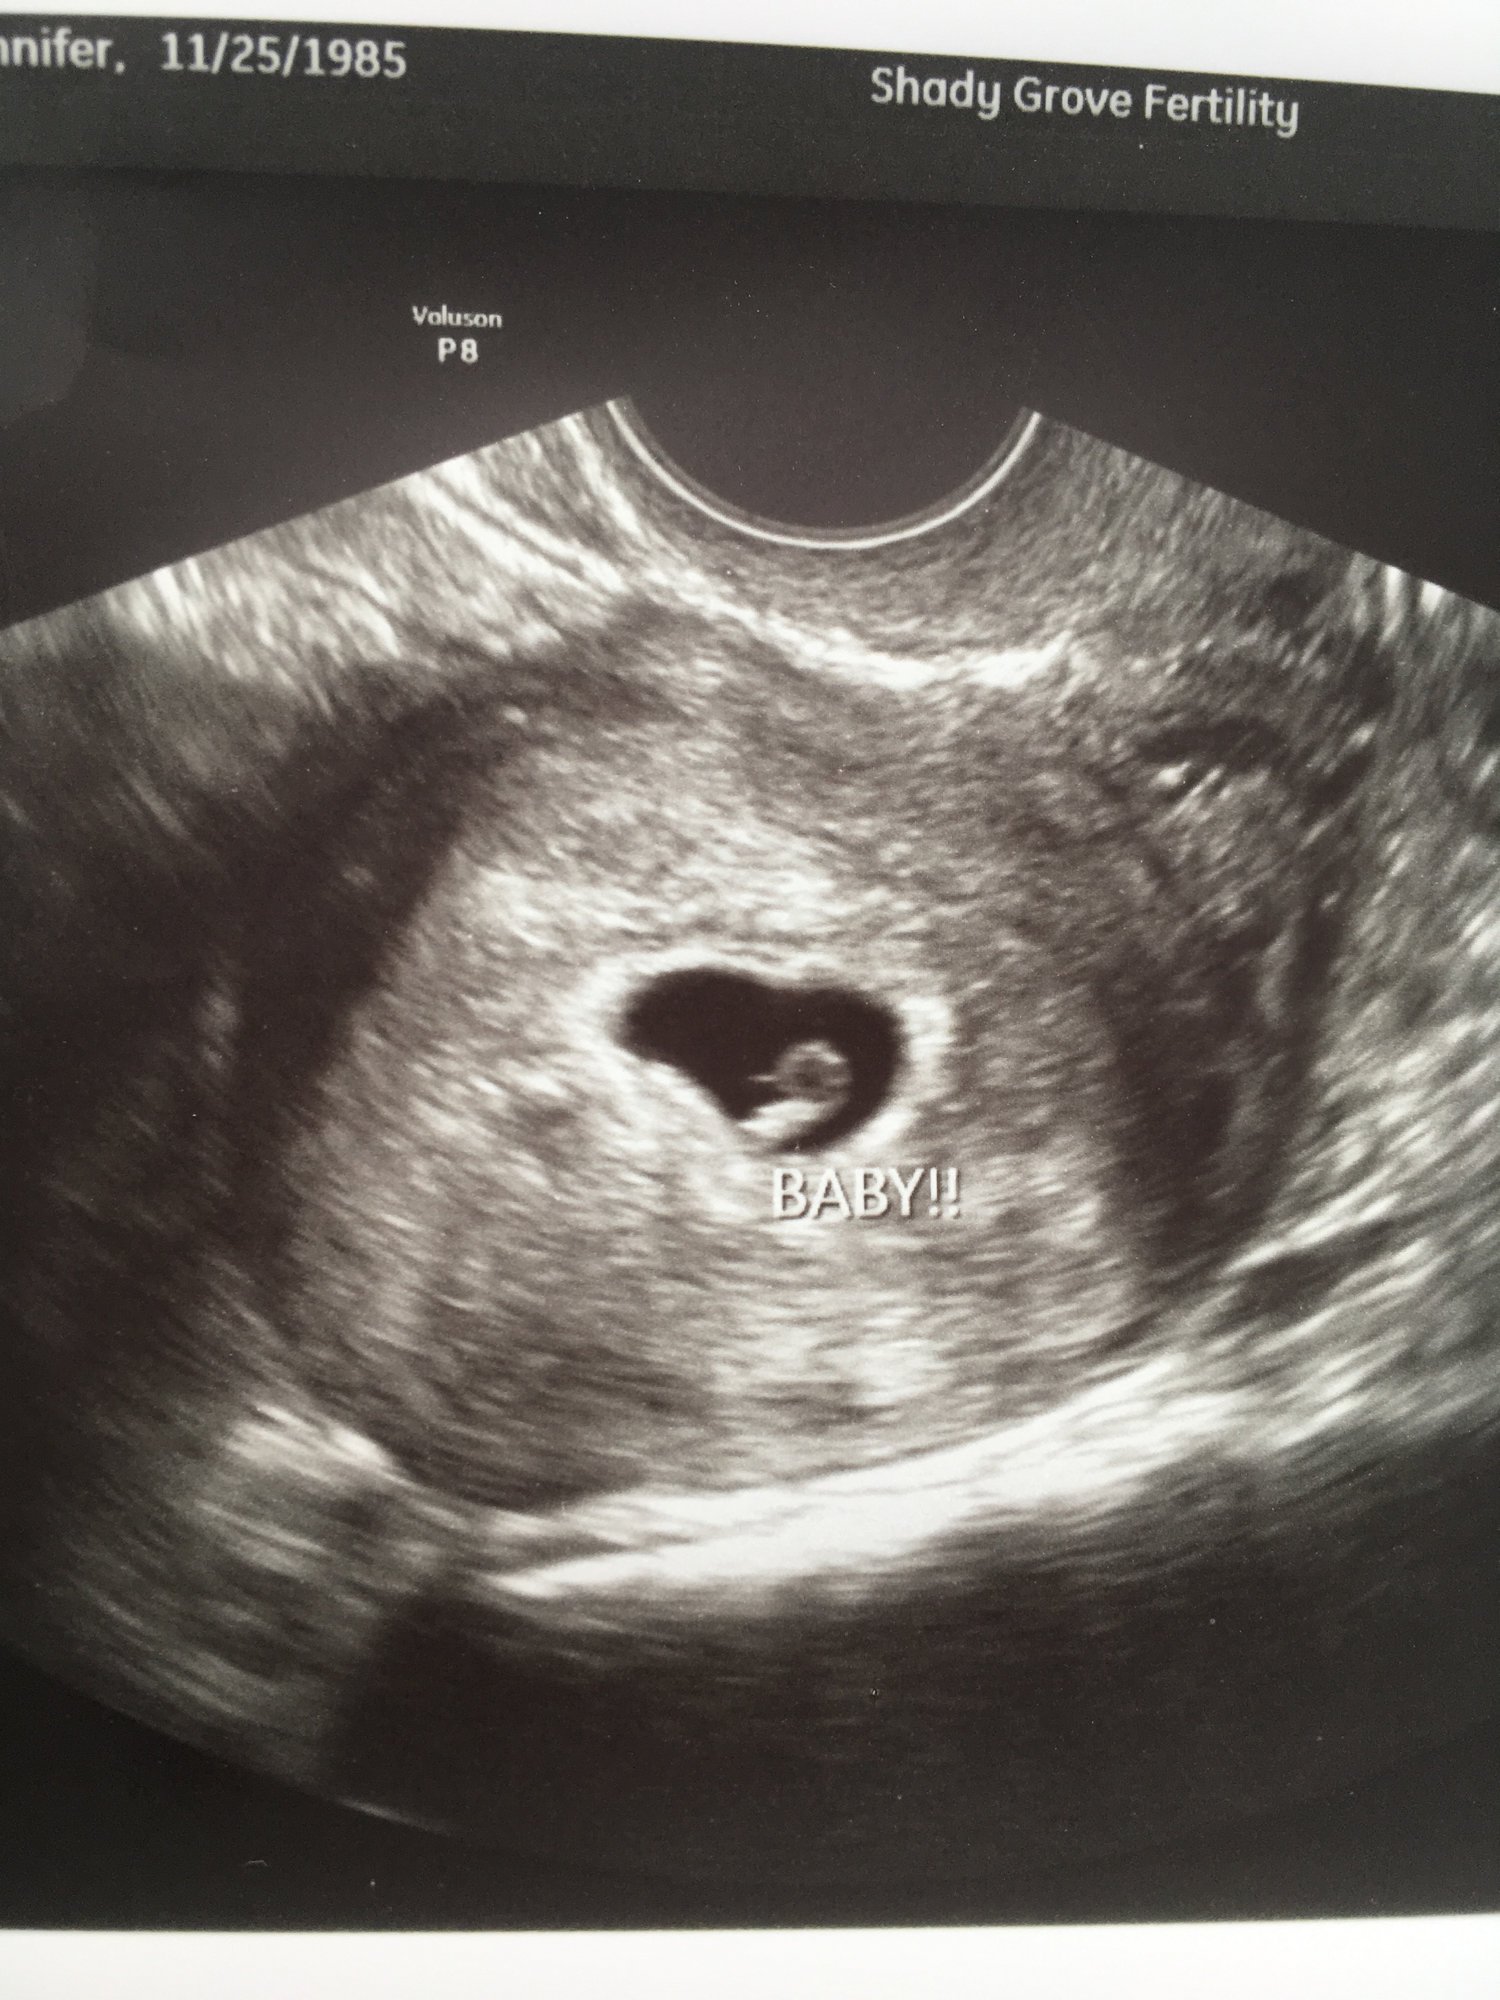

6+1 with a strong (and very new!) heartbeat!

After 2 miscarriages last year, this is what I needed today!